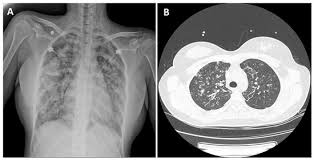

- Chest X-ray – A chest X-ray can show signs of lung inflammation, such as fluid accumulation or changes in lung tissue.

- CT scan – A more detailed imaging test that provides a clear picture of lung abnormalities.